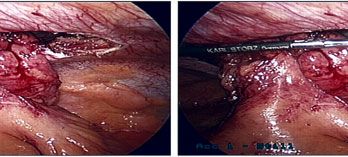

Uncommon type of ventral hernias which occurs mainly in patients who have ileostomy or colostomy, can be managed by minimally invasive surgery.